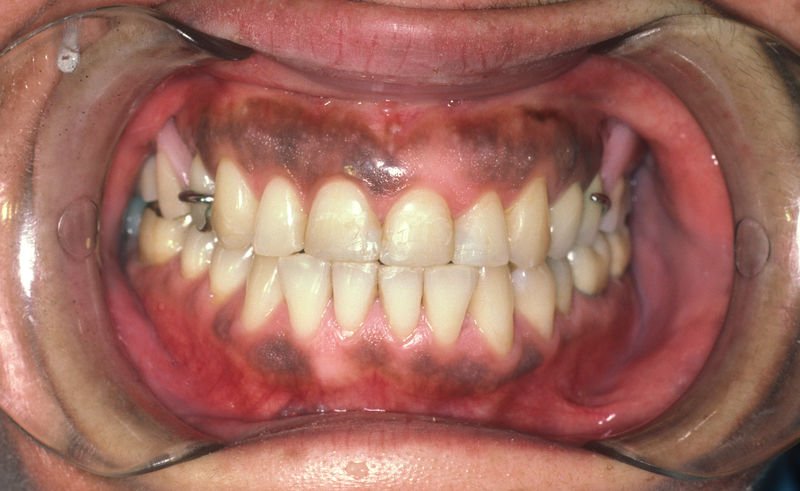

Proceso fundamental y exhaustivo que realiza el odontólogo para identificar la condición de la cavidad oral e identificar tanto zonas que esten sanas como aquellas que no lo son y buscar la causa de cualquier enfermedad o anomalía en la cavidad oral. No se limita a buscar caries, sino que ofrece una evaluación integral que sirve de base para diseñar un plan de tratamiento adecuado, efectivo y personalizado.

Secuencia de procedimientos que el profesional de la salud propone al paciente para tratar o controlar una enfermedad o condición específica. Es una guía estratégica que transforma el diagnóstico en acciones terapéuticas para alcanzar un objetivo de salud predefinido.

Implantes, ortodoncia y coronas.

Ortodoncia y coronas.

Cirugía ortognática, implantes, carillas y coronas,